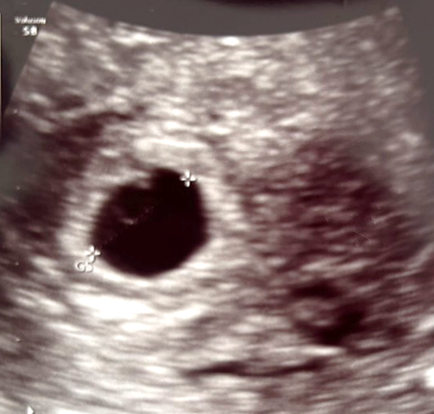

今回の胎嚢写真がこちらです。

なんとなく丸型リングが見えるような気がしますが、これが「卵黄嚢」なのかの言及がありませんでした。

胎嚢8mmで「卵黄嚢」は見えるのか

調べてみる卵黄嚢がはっきり丸く見えるのは胎嚢が10〜12mmを超えた頃 が一般的のようです。

胎嚢が8mmということは、「影のように見えるだけ」は普通の範囲とのこと。